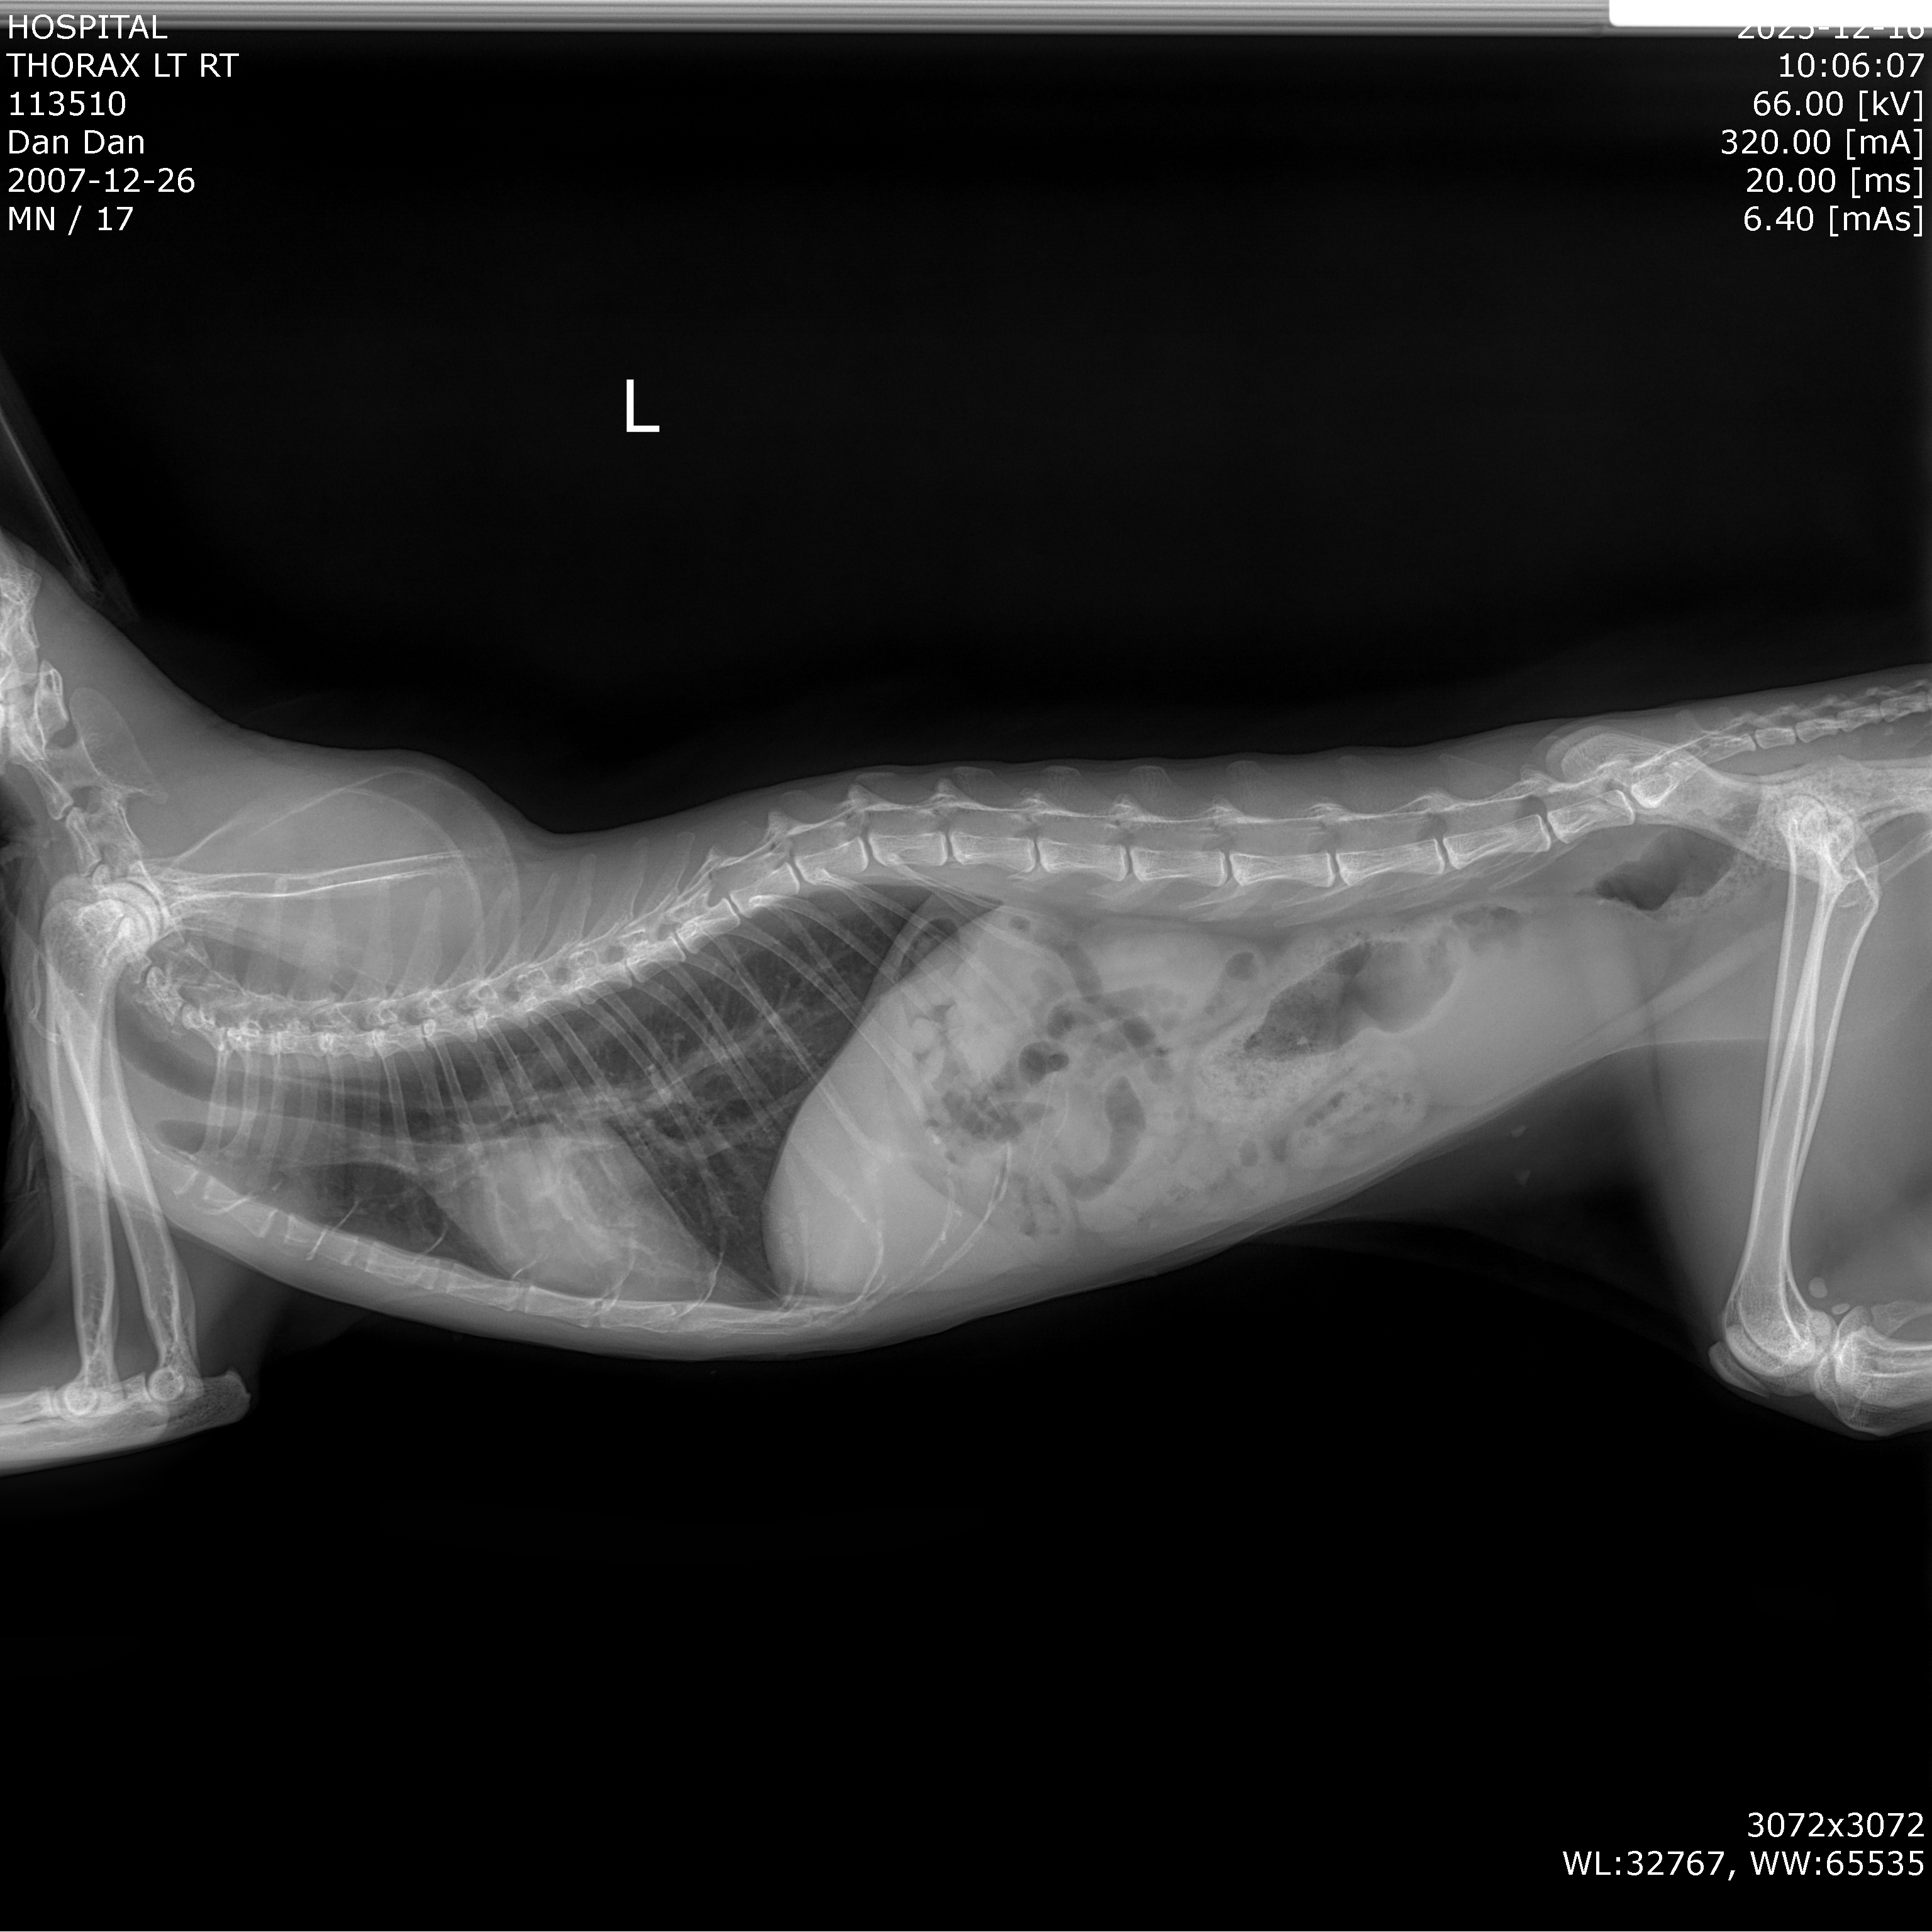

Dan Dan underwent both echocardiography and thoracic radiography.

Findings:

The heart structure had undergone irreversible changes. The heart was overloaded and had entered heart failure.

Dan Dan’s life was at imminent risk.

Dan Dan was in Stage C, already experiencing heart failure.

After the emergency intervention, Dan Dan was no longer in immediate danger.

With appropriate long-term medication, her condition stabilized.

Dan Dan continued regular follow-ups.

Results showed:

She returned to a stable daily routine — eating, drinking, and moving independently.

This is considered clinical stability.